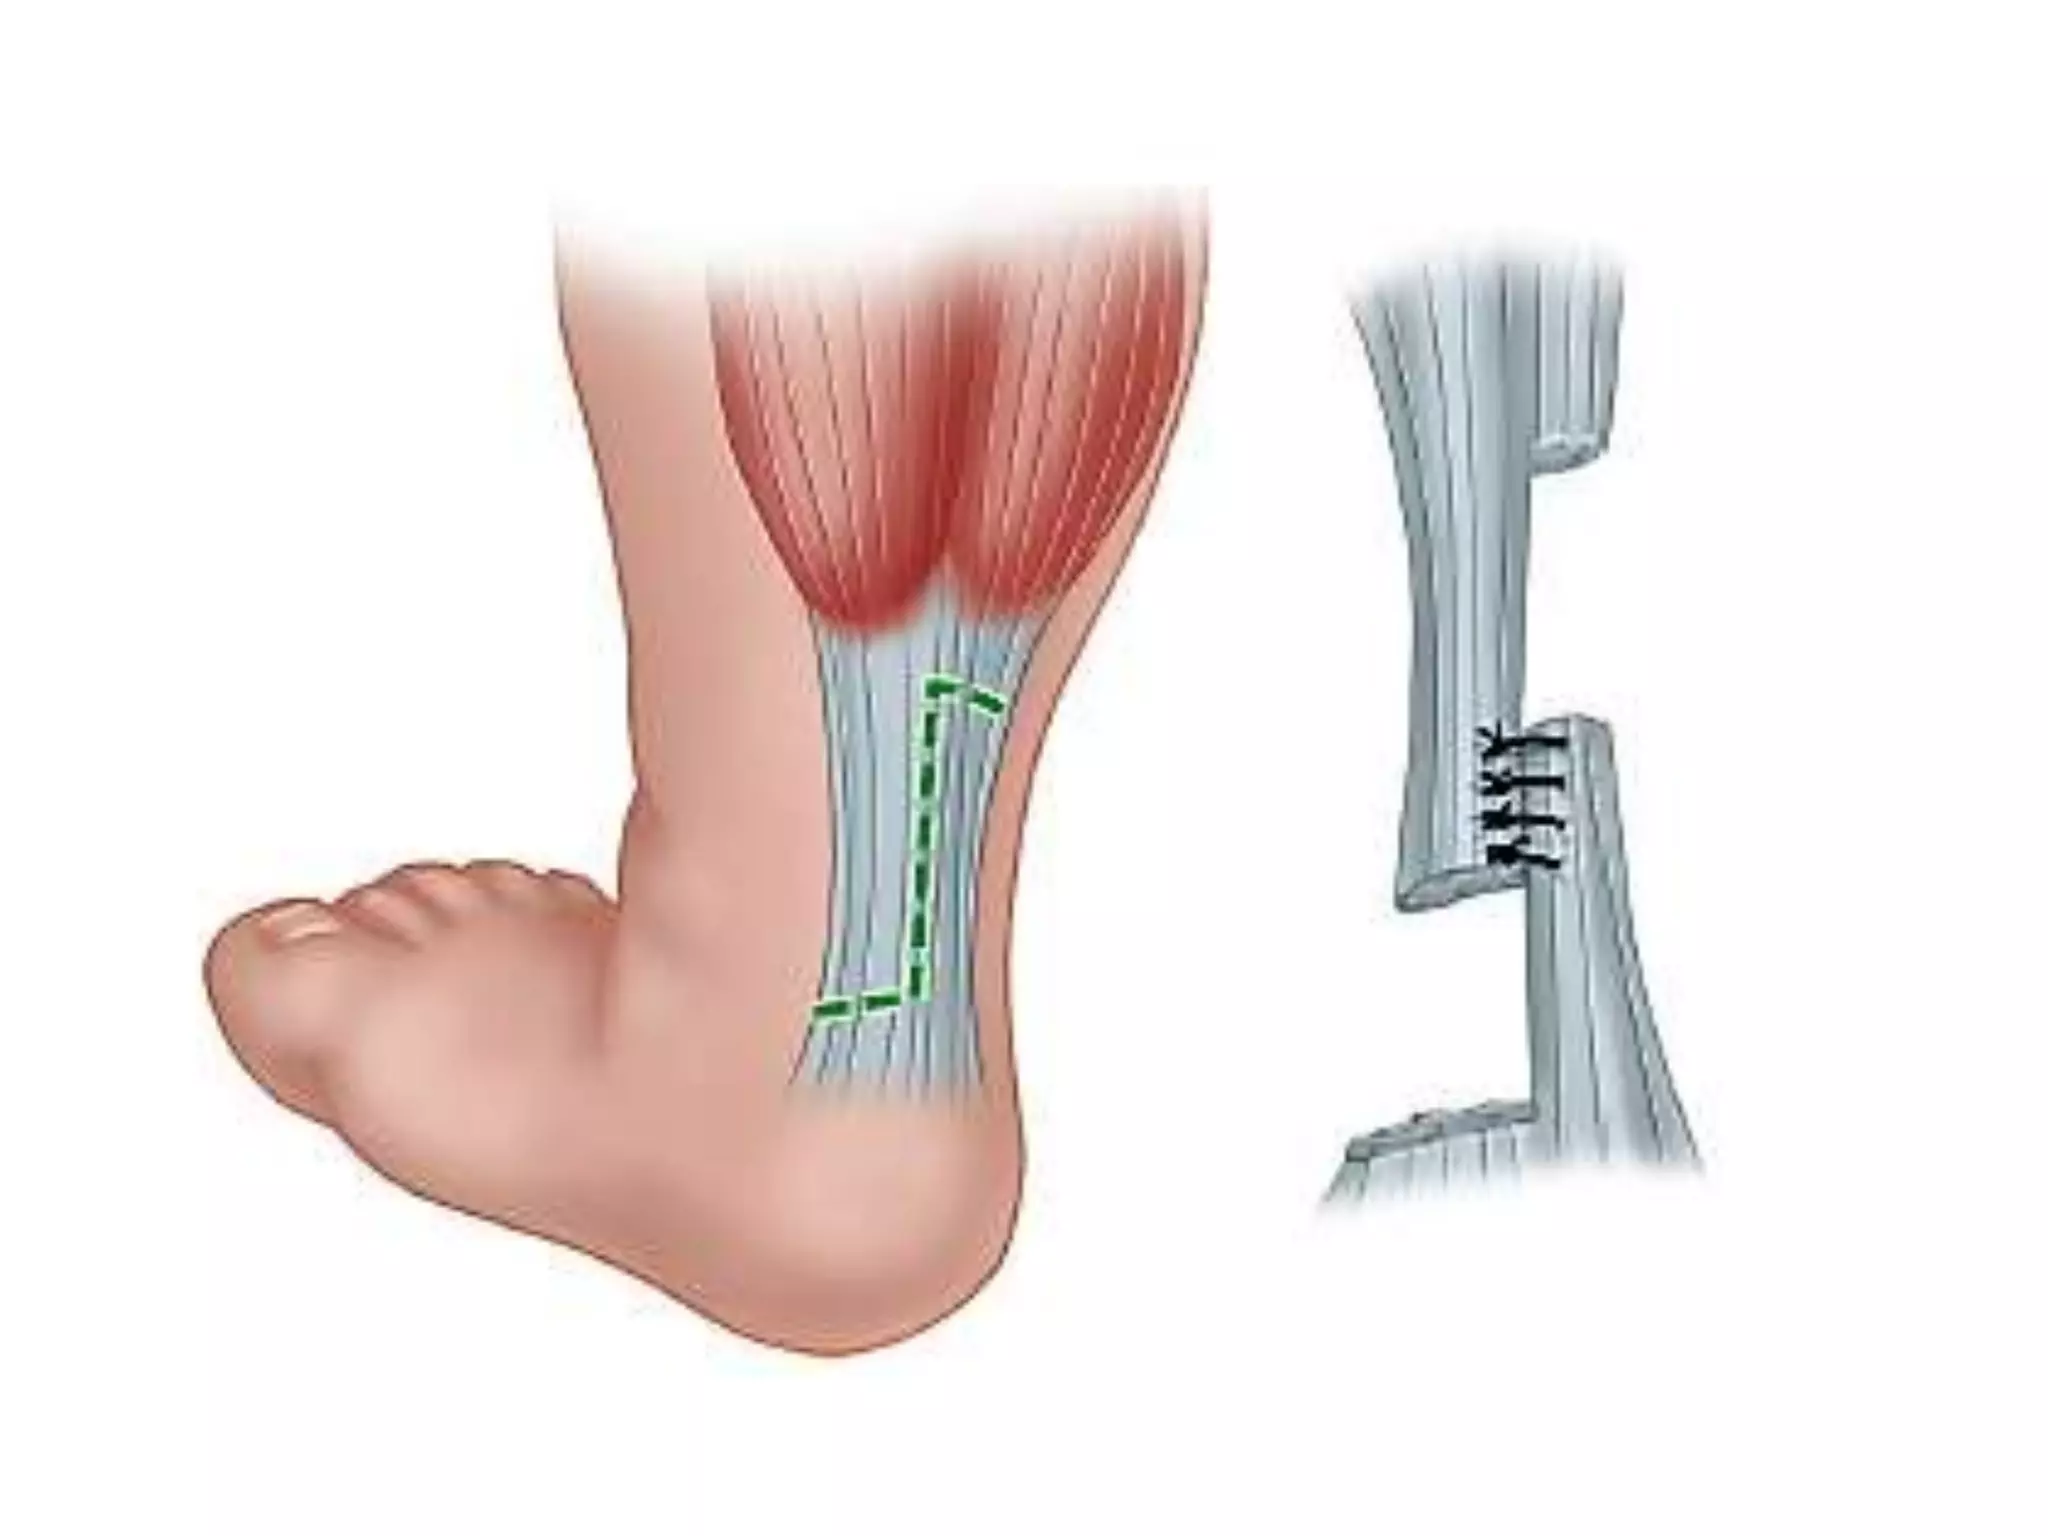

Tenotomy

• Indicated to correct equinus when cavus,

adductus, and varus fully corrected but ankle

dorsiflexion remains less than 10 degrees

above neutral

• to facilitate more rapid correction,

subcutaneous heel cord tenotomy is performed-

entire Achilles tendon is transected

• Performed in children up to 1 year of age

without the occurrence of overlengthening or

weakness

• Foot is held by an assistant in maximum

dorsiflexion

• select a site about 1.5 cm above the

calcaneus for the tenotomy

• The blade enters the skin along the medial

border of the Achilles tendon.

• Successful tenotomy -palpable pop and

ability for further dorsiflexion of about 15 to

20 degrees

Post-tenotomy cast

• Foot abducted 60 to 70 degrees with respect

to the frontal plane of the ankle, and 15

degrees dorsiflexion.

• for 3 weeks

• Usually the last cast